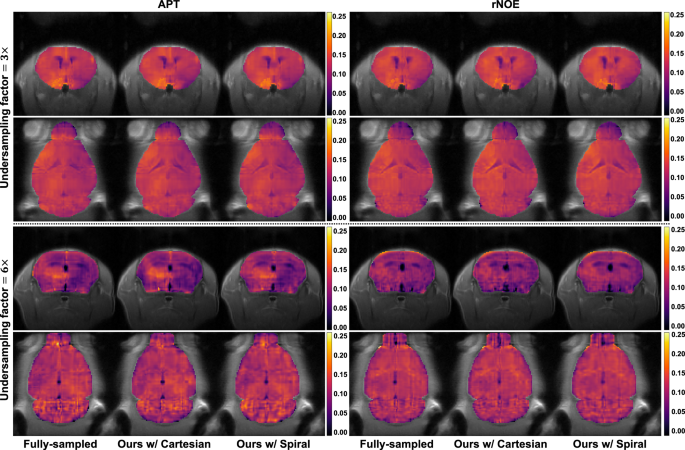

Figure 3 displays Z-spectra derived from fully sampled and reconstructed CEST images. The reference spectra \({Z}_{{{\rm{ref}}}}\), Z-spectra \({Z}\), and Lorentzian difference spectra \(\Delta Z\) are plotted using dotted, solid, and dashed lines, respectively. Two representative regions of interest, i.e., the cortex and cerebrospinal fluid (CSF), are analyzed, and the residuals between fully sampled and reconstructed Z-spectra are plotted for comparison. The reconstruction error remains below 0.5% across most frequency offsets; however, elevated errors occur near 0 ppm, potentially due to the rapidly varying image intensities in this region. Figure 4 displays two CEST maps: amide proton transfer (APT) and relayed nuclear Overhauser enhancement (rNOE). APT, derived from \(\Delta Z\) at 3.5 ppm, reflects amide group distribution, while rNOE, obtained from \(\Delta Z\) at −3.5 ppm, detects macromolecules such as membrane lipids66,67. CEST maps from our method exhibit strong agreement with the fully sampled ones.

Rodent brain imaging with different acceleration rates

Normal rodent brain imaging was performed on a pre-clinical scanner, and a total of eight male C57BL/6 mice were used. We acquired 60 CEST scans with an echo-train-length (ETL) of 32 and 16 CEST scans with an ETL of 16. The ETL-32 CEST scans have \({N}_{{{\rm{shot}}}}\) of 3 and were used for 3\(\times\) undersampling. The ETL-16 CEST scans have \({N}_{{{\rm{shot}}}}\) of 6 and were used for 6\(\times\) undersampling. Out of 60 ETL-32 CEST scans, 48 were randomly selected for training and validation, while the remaining 12 were reserved for testing. For the ETL-16 CEST scans, four-fold cross-validation was performed. The k-space of each CEST scan was retrospectively undersampled via complementary undersampling. In the case of the Cartesian trajectory, for 3\(\times\)/6\(\times\) undersampling, 16/8 lines were sampled at the center of k-space, which concentrates most energy of the MRI signal. The remaining peripheral k-space was sampled by \({N}_{{{\rm{adj}}}}\) adjacent frequency offsets in a cyclic manner. Therefore, \({N}_{{{\rm{adj}}}}=5\)/\({N}_{{{\rm{adj}}}}=11\) adjacent frequency offsets were used to fully cover peripheral k-space for 3\(\times\)/6\(\times\) undersampling. In the case of a spiral trajectory, the leaf-length \(L\) was varied to simulate different undersampling factors, while \({N}_{{{\rm{adj}}}}\) was kept at 6 in the experiments. We adopted a variable-density spiral sampling pattern63 and the gradient amplitude and slew rate limit were set to 8 G/cm and 90 G/cm/ms, respectively, resulting in a leaf-length \(L\) of 3185/1504 under 3\(\times\)/6\(\times\) undersampling.

We compared the reconstruction performance of the proposed method with a conventional compressed sensing-based method (CS-Wavelet50) and four deep learning-based reconstruction methods. Different methods use different k-space sampling patterns and network structures: (1) PROPELLER-CEST53 uses PROPELLER trajectory64 and U-Net for image reconstruction; (2) AMO-CEST55 designs a pseudo-radial trajectory and uses attention U-Net for image reconstruction; (3) DLSR-CEST39 samples center of k-space and uses a deep residual channel attention network65 for image reconstruction; (4) CEST-VN54 uses a data-sharing Cartesian trajectory and a variational network for image reconstruction. The number of trajectory points \(L\) was kept consistent across different methods to ensure the same undersampling factors.

The quantitative evaluation results for all compared methods are summarized in Table 1, which lists the average and standard deviation of PSNR and SSIM for both 3\(\times\) and 6\(\times\) undersampling. Our method outperforms all compared methods for both Cartesian and spiral k-space trajectories. In addition, we performed Wilcoxon signed-rank tests on both PSNR and SSIM results, yielding \(p\)-values of \(p\ll 0.0001\) for all compared methods, i.e., statistical significance. Figure 2 shows qualitative evaluation results of all compared methods. The reconstructed images and their corresponding error maps (relative to fully sampled images) are shown. The error maps are computed using the formula \(100 \% \times \left|\hat{x}-x\right|/{\max }_{95 \% }\left(x\right)\), where \(\hat{x}\) represents the reconstructed images, and \(x\) denotes the fully sampled images. All error maps are displayed using the same color scale. Our method achieves higher consistency to fully sampled images, with enhanced image fidelity and fewer structural distortions visible in error maps.